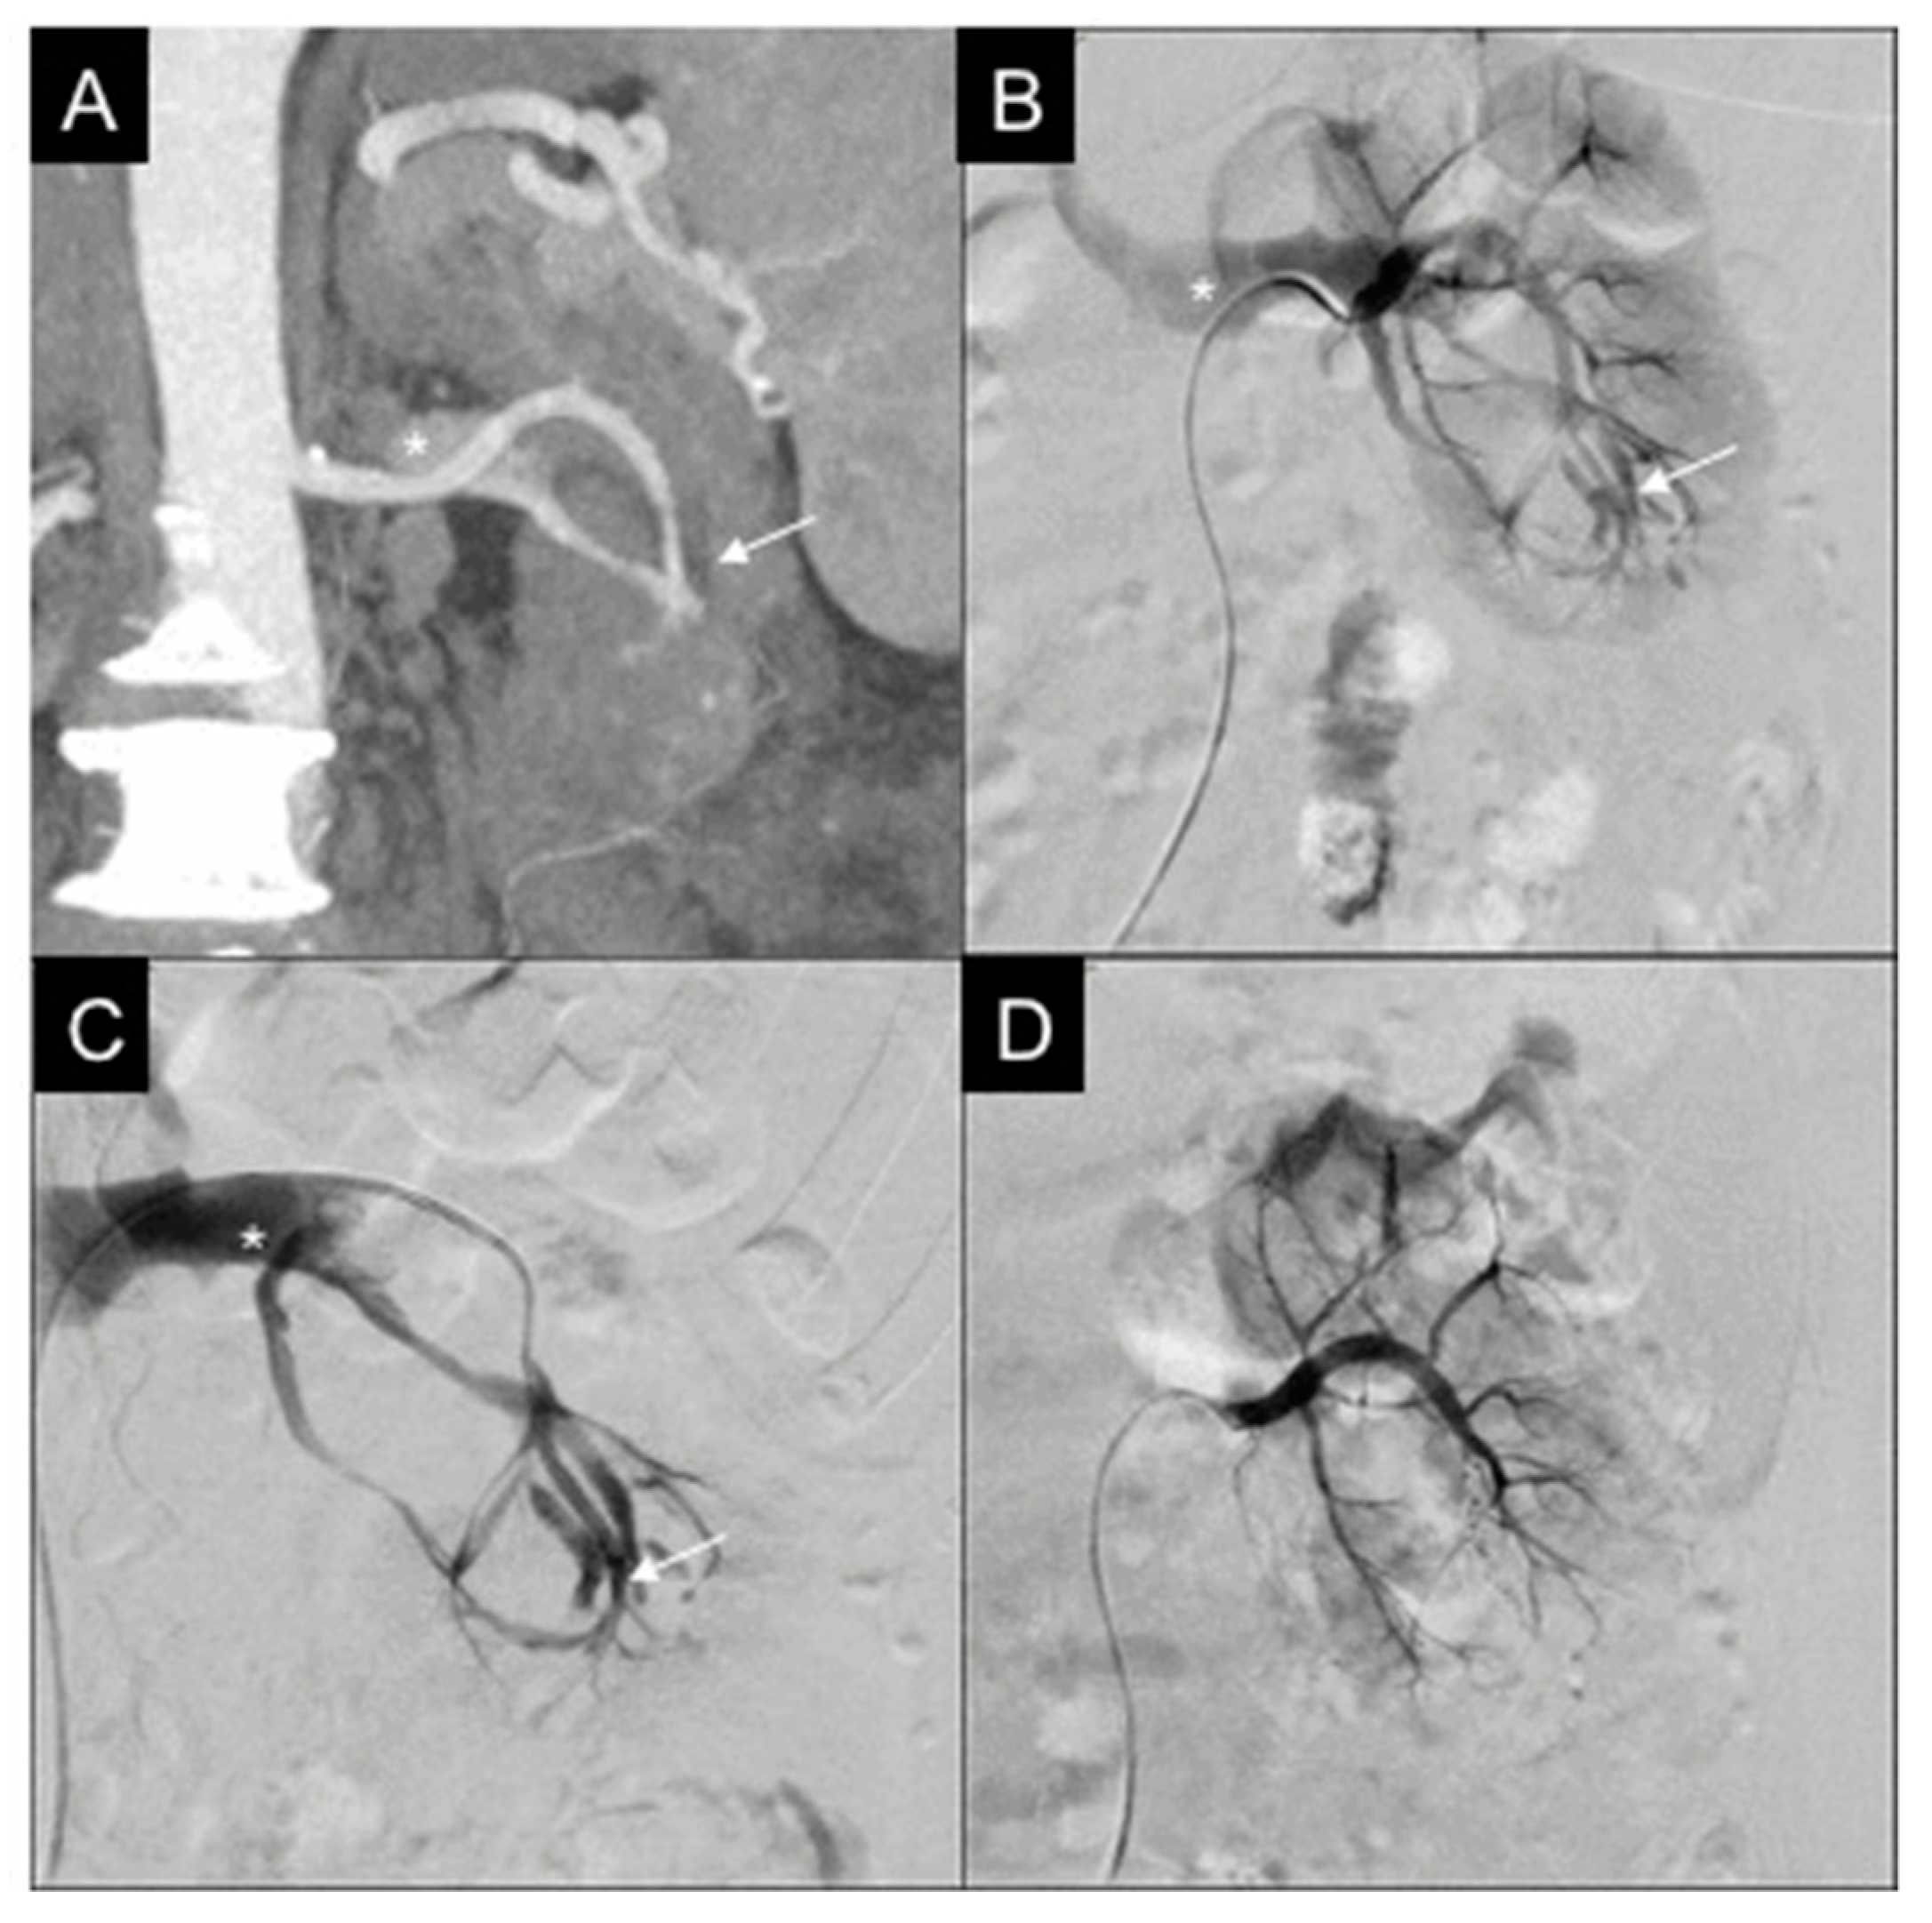

3.2. CT-DSA Correlation

| Type of lesion at CT | 13 PA |

| 12 active blushes | |

| 1 AVF | |

| 1 negative | |

| Type of lesion at DSA | 15 PA |

| 9 active blushes | |

| 1 active blush + PA | |

| 1 active blush + AVF | |